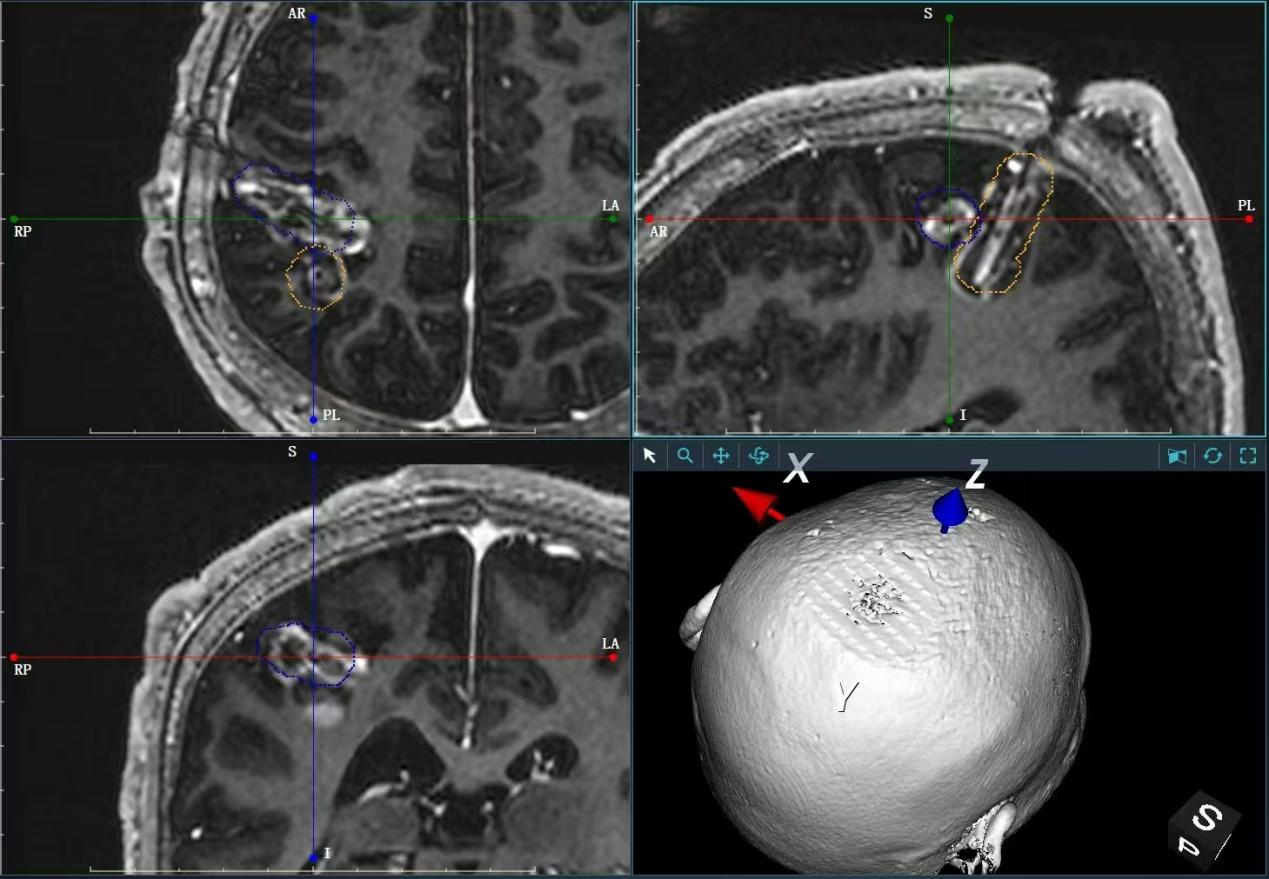

手术中,医生仅在患儿颅骨上钻开一个约3毫米的微孔,随后将直径不足2毫米的柔性激光光纤植入颅内。在磁共振全程实时引导下,光纤被精准送达病灶核心。

激光治疗过程图示

在消融阶段,系统以41℃~45℃的温度对病灶进行可控加热。术中磁共振连续扫描,实时生成三维温度分布图并投射于手术屏幕,使医生能够同步观察消融范围,确保其严格限定在病灶边界内,不损伤周边正常神经纤维。